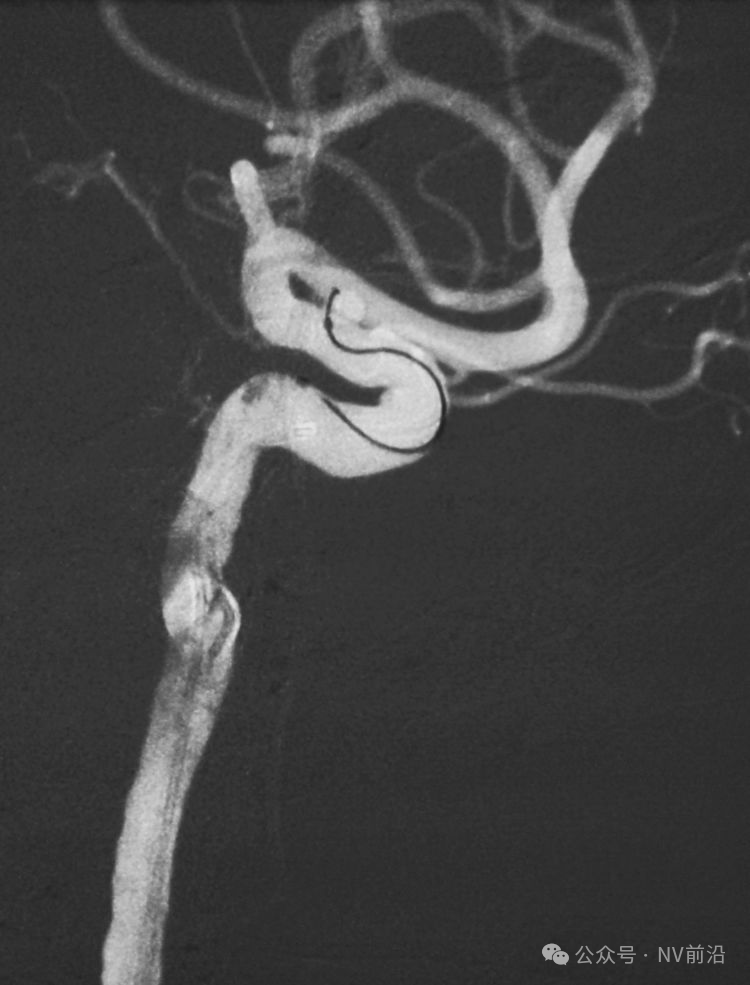

术后左颈内动脉工作位造影和蒙片。

术后左颈内动脉造影三维重建显示动脉瘤消失。